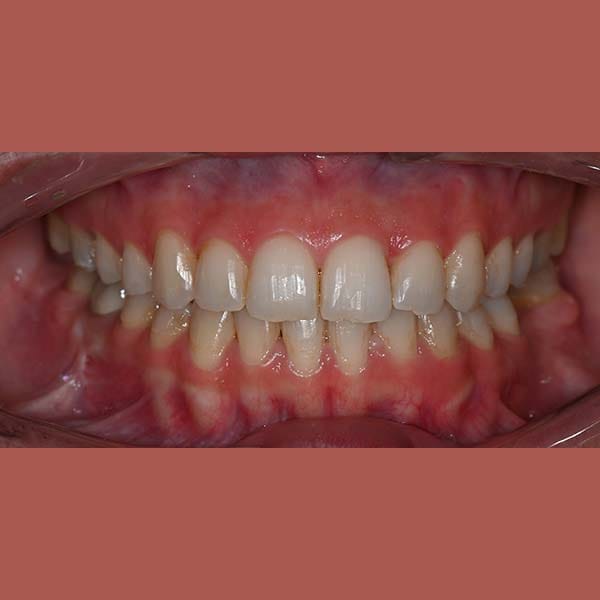

كما تظهر الصور، كانت النتيجة تحولاً كاملاً. تم استعادة الشكل الطبيعي للذقن والفك السفلي، وتم تصحيح العضة المعكوسة. في النهاية، أصبح بإمكان مراجعتنا الشابة أن تستمتع بابتسامة مميزة وواثقة وملامح وجه متناغمة.